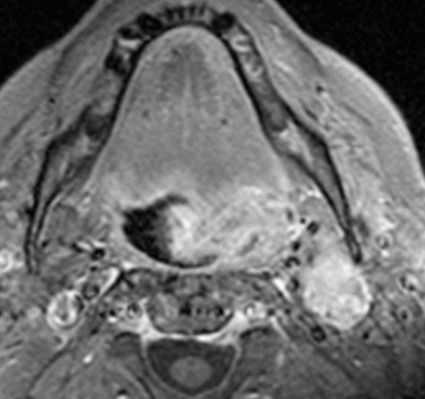

Плоскоклеточный рак гортаноглотки наиболее часто включает грушевидные синусы. Раки, которые возникают в этом месте, как правило, долго не проявляются и очень агрессивные. Они прорастают в глубокие пространства и сразу поражают многочисленные лимфатические узлы. Опухоль может прорастать хрящ и даже гортань. При МРТ мягких тканей правильная оценка характера роста плоскоклеточного рака гортаноглотки очень важно для стадирования процесса и хирургической тактики лечения.

Что касается глубинных структур, особое внимание при МРТ мягких тканей шеи следует уделить распространению опухоли на превертебральное пространство. Инвазия глубокой фасции шеи, длинных мышц шеи, или самого позвоночника, определяемые при МРТ мягких тканей шеи, ставят вопрос об обширной операции. Кроме того, поражение сонной артерии ставит вопрос о резектабельности. Некоторые хирурги считают, что если опухоль по данным МРТ мягких тканей шеи охватывает меньше 50% сонной артерии она может быть от нее отделена. Вероятность невозможности удаления опухоли заметно увеличивается, когда по данным МРТ мягких тканей шеи она окружает более 75% сонной артерии. Вовлечение в процесс жевательного пространства может происходить с ротоглотки. Вовлечение жевательного пространства должно насторожить в плане прорастания основания черепа, особенно, через овальное окно и/или вдоль крылонебной ямки. Другие пути распространения через основание черепа идут вдоль сонного канала, через яремное отверстие, и евстахиеву трубку

МРТ мягких тканей шеи с контрастированием. Распространение опухоли корня языка на каротидное пространство.